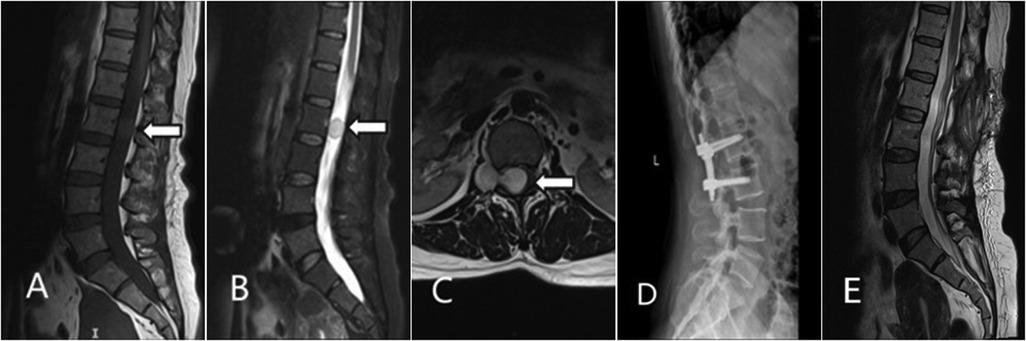

Background: Ganglioneuroma (GN) of the lumbar spine is rare, typically occurring in children and young adults. Its diagnosis in middle-aged patients can be challenging. This paper reports a case of a dumbbell-shaped lumbar GN in a middle-aged woman. Case: A 46-year-old woman presented with low back pain and radiating leg pain. MRI revealed a dumbbell-shaped mass at the L2 level. She underwent posterior microscopic total tumor resection with L2-L3 pedicle screw fixation. Postoperative pathology confirmed GN. Conclusion: At the 1-year follow-up, there was no recurrence. For dumbbell-shaped lumbar GN, a posterior approach combined with internal fixation is an effective strategy. This case suggests that GN should be considered in the differential diagnosis of foraminal masses in middle-aged patients.